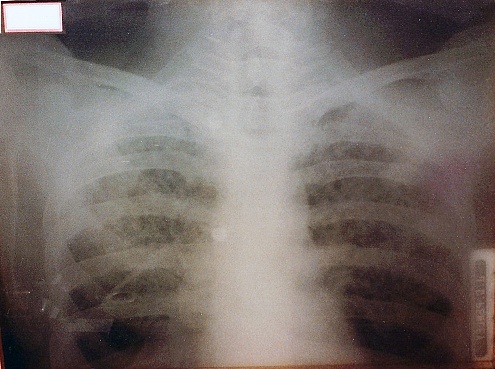

Estimated Date: 1920

Name: Glass X-Ray Plate

Manufacturer: Unknown

Description: This chest x-ray of a patient with Tuberculosis from 1920 is printed on glass. The term “flat plate” arose from the original practice of using glass plates instead of film for printing X-Rays. The plate is 11“x 14” and has a paper label indicating a 6 second exposure.